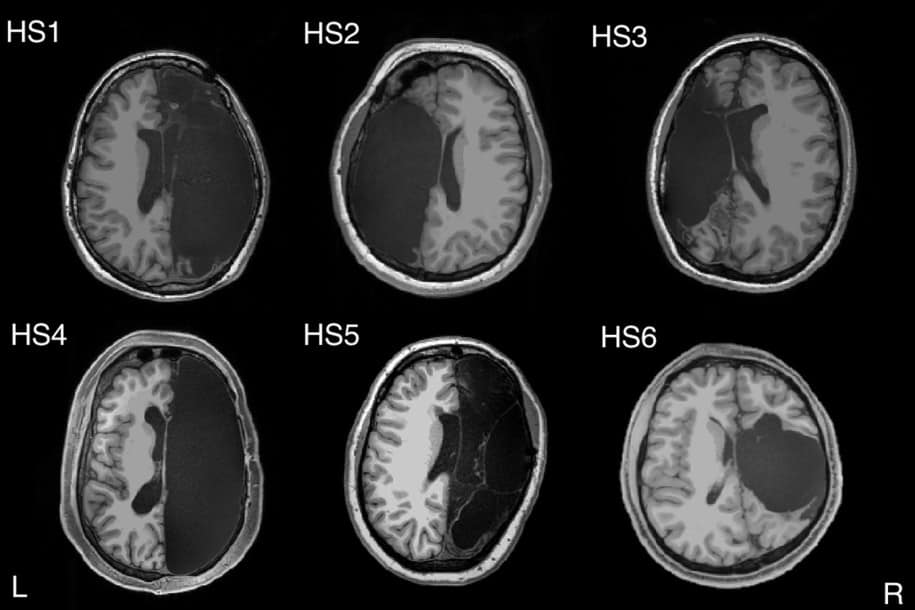

Seperti dikutip Telset.id dari New York Post, Kamis (21/11/2019), pemindaian baru nan luar biasa dari enam pasien mengungkapkan bahwa manusia ternyata masih bisa hidup dengan separuh otak. Begini penjelasan ilmiahnya.

Satu hemisfer otak enam pasien itu dihapus selama masa kanak-kanak untuk mengurangi kejang epilepsi parah. Pemindaian terhadap mereka menunjukkan bagaimana otak secara ajaib dapat memutar ulang dirinya sendiri.

Tujuannya untuk membantu tubuh berfungsi seolah-olah otak tidak utuh. Studi kasus tersebut, mengungkapkan bahwa otak membuat hubungan yang luar biasa kuat dia antara jaringan fungsional otak yang berbeda-beda.

Enam pasien yang dilibatkan dalam penelitian berusia 20-an tahun dan awal 30-an tahun. Mereka berusia tiga bulan sampai 11 tahun manakala mengalami penghapusan setengah otak untuk mengurangi kejang epilepsi parah.

Dokter mengira pemindaian akan menemukan koneksi yang lebih lemah dalam jaringan tertentu di orang yang hanya punya satu belahan otak. Ternyata, konektivitas global mereka normal. Koneksi antara jaringan berbeda cukup kuat.